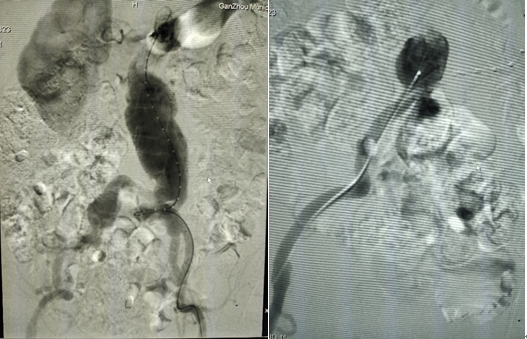

7.主體支架釋放后造影,左右髂動(dòng)脈分支通暢

8、調(diào)整好左右兩邊導(dǎo)管導(dǎo)絲,引入左右髂動(dòng)脈分體支架

9、主體支架和左右分體支架釋放后,發(fā)現(xiàn)支架貼合不佳,球囊后擴(kuò)

10、在3D打印血管的輔助下完成腹主動(dòng)脈瘤的覆膜支架腔內(nèi)隔絕術(shù),最后造影結(jié)果